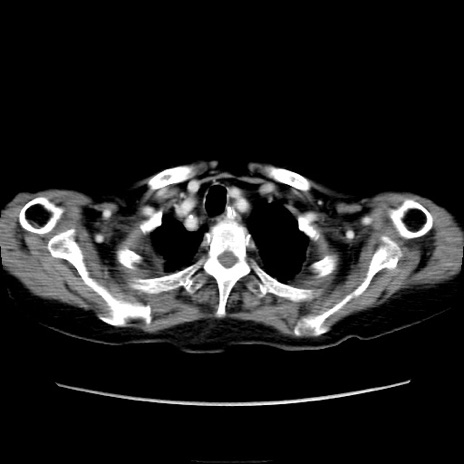

症例40(横断像)

【症例】90歳代女性

【主訴】腹痛・嘔吐

【現病歴】 食欲低下、嘔吐があり昨日他院受診。肺炎と診断され入院となる。入院後より腹部全体に圧痛あり。胃管留置され経過みていたが、症状持続するため、

当院転院となる。

【既往歴】胸椎圧迫骨折、胆石症

【身体所見】腹部:中央に激痛あり、圧痛あり、反跳痛不明

【データ】WBC 17100、CRP 18.82

横断像